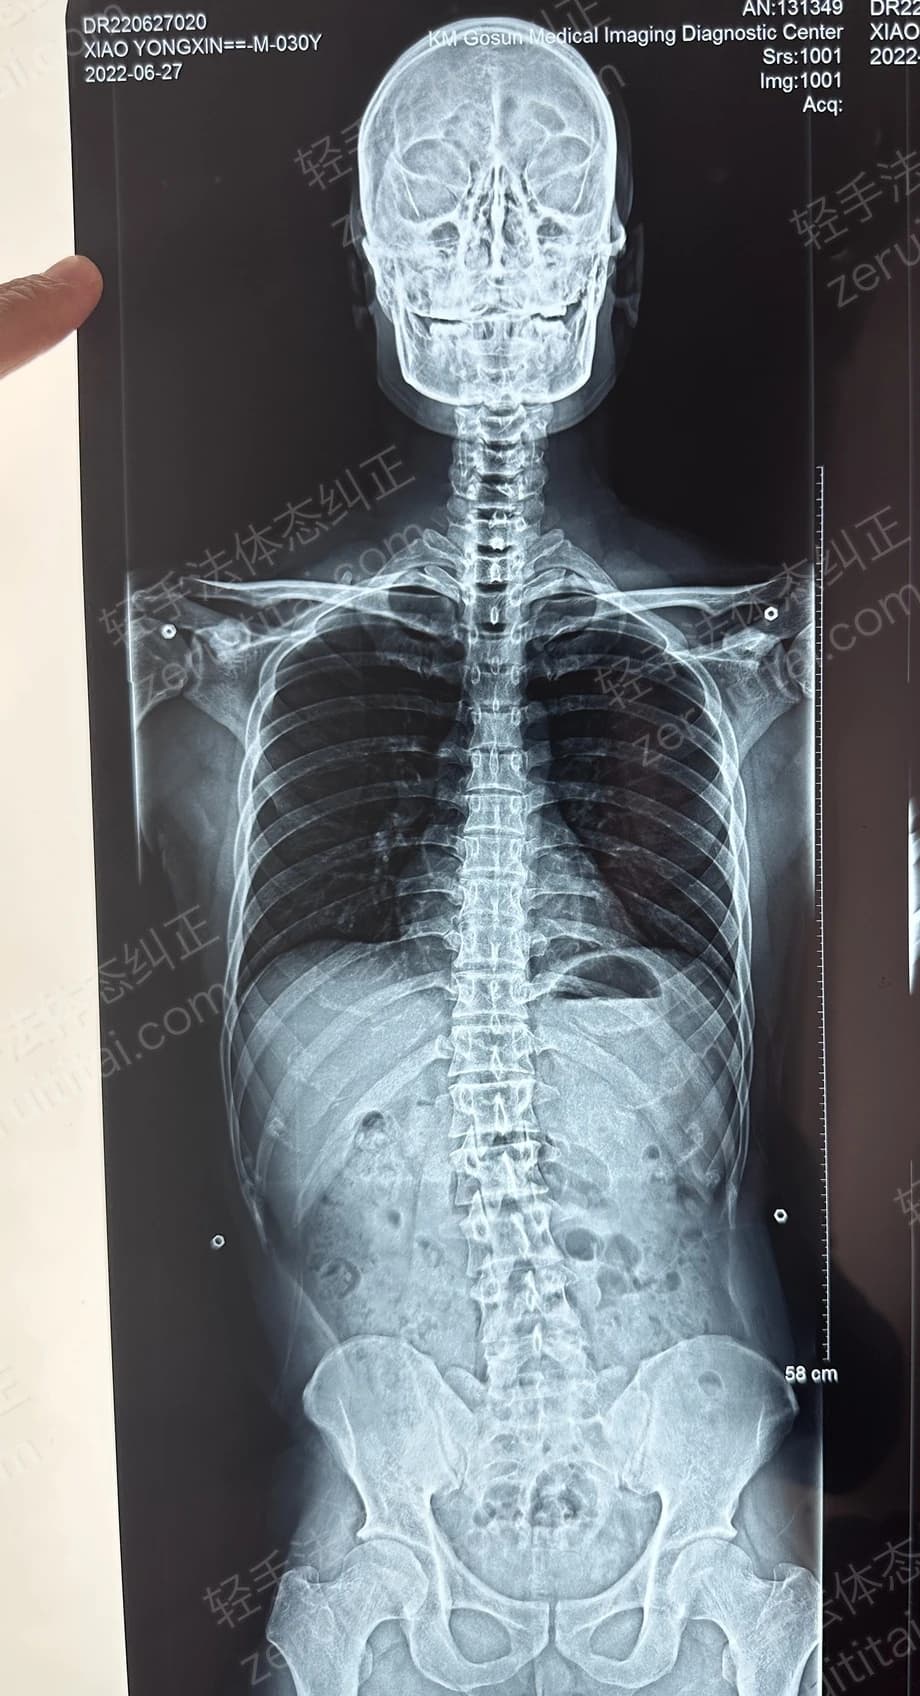

2022.06.27

第 1 次记录